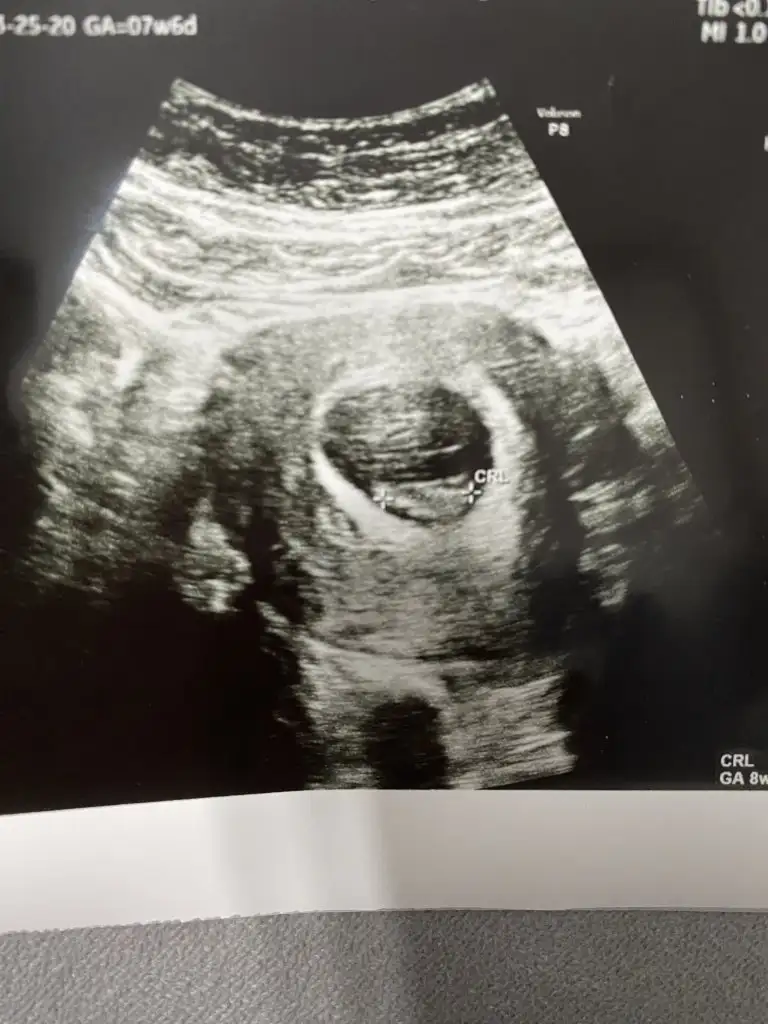

Kızlar 6hafta 4 gün hatta 2 gün olarak güncellebiliriz dedi doktor. Karından. Sağ tarafımdan baktı. Benim içinde bi yorumda bulunabilir misiniz

• A4C97739-4859-4FC0-9A10-E1E4218CAAD6.webp

Aynı yere tutunmuş aynı zamanda çekilmiş ultrason resmine baktım şimdi benimki oğlan oldu canım . Sanırım seninki de erkek bu teoriye göre z